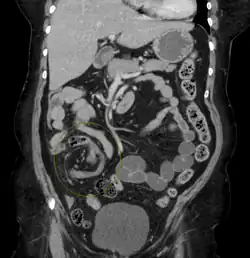

Plain X ray of a cecal volvulus -

CT scan of a cecal volvulus